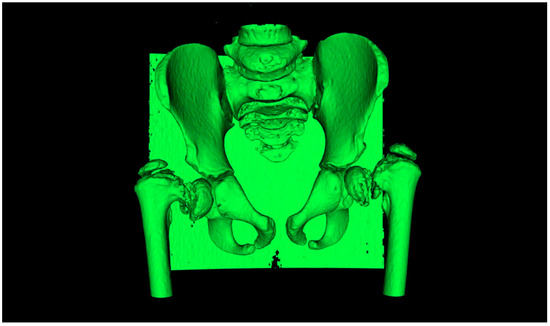

2.1. Case Study

2.2. CAM and CAD-CAT

2.3. CASS and CCG Design